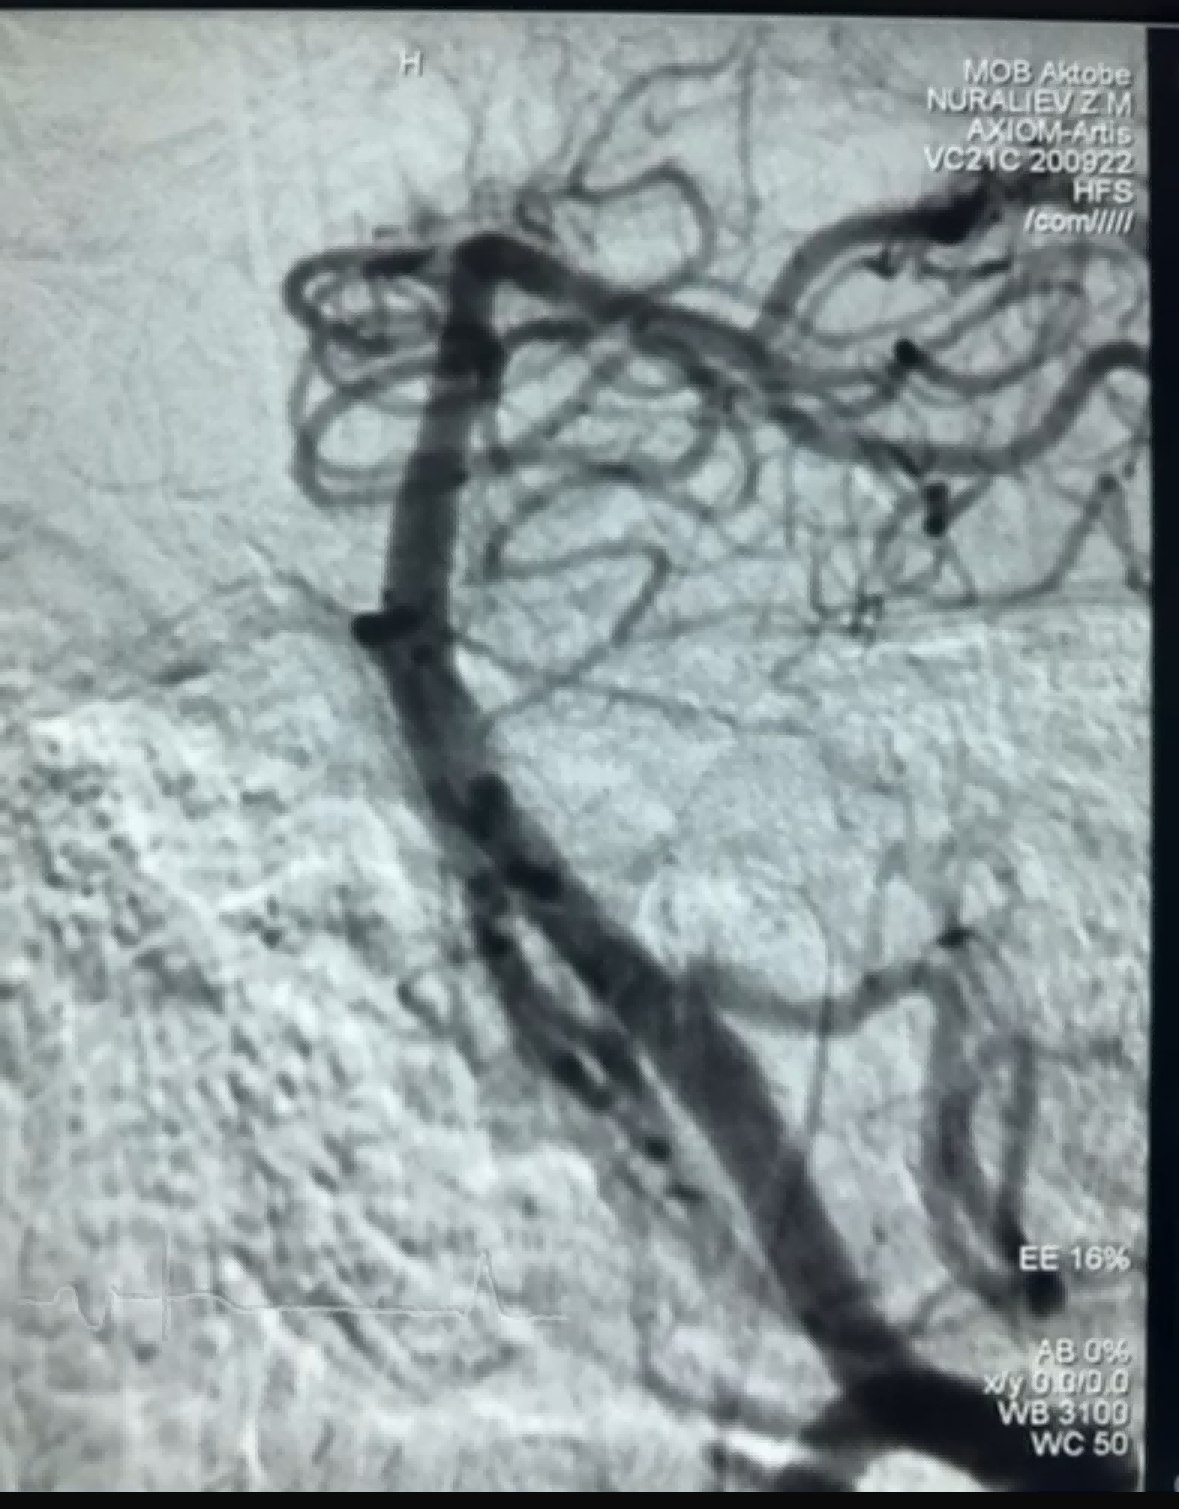

Recentemente, houve um caso bem-sucedido de trombectomia usando o Dredger Stent Retriever da NeuroSafe Medical Co., Ltd. O Dredger Stent Retriever tem uma ponta macia não invasiva, o que reduz muito o risco de danos à íntima, e tem um design exclusivo de orifício com formato especial que captura coágulos sanguíneos principalmente prendendo as mudanças de espaço.